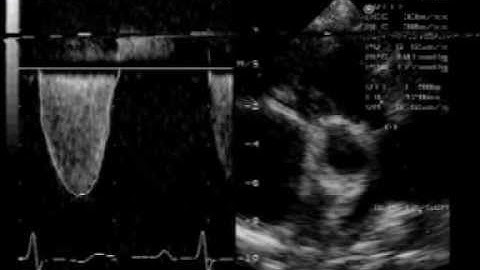

Kosmos Continuous Wave (CW) Doppler